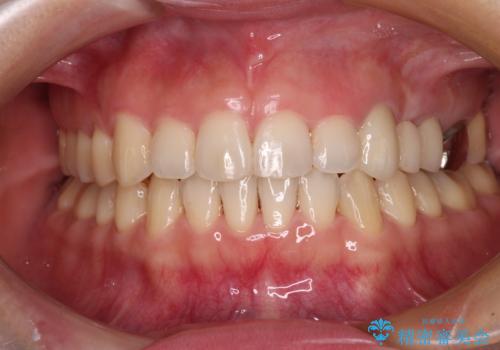

当初は奥歯のみの治療をご希望でしたが、話を進めていくうちに、軽度ではあるものの、幼少期の薬の影響で歯が変色していることがコンプレックスであるということが分かりました。

長年歯の色が塞ぎ込んでいた部分があるとのことで、これを機会に全ての歯を真っ白にするために、オールセラミッククラウンにて補綴治療を行うこととしました。

より白さが目立つように、自然な仕上がりではなく、作り物の雰囲気があるフルジルコニアクラウンにて補綴治療を行いました。